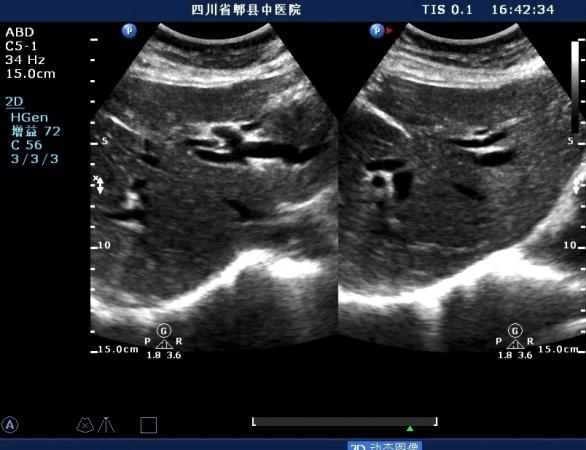

胆总管胰腺段结石